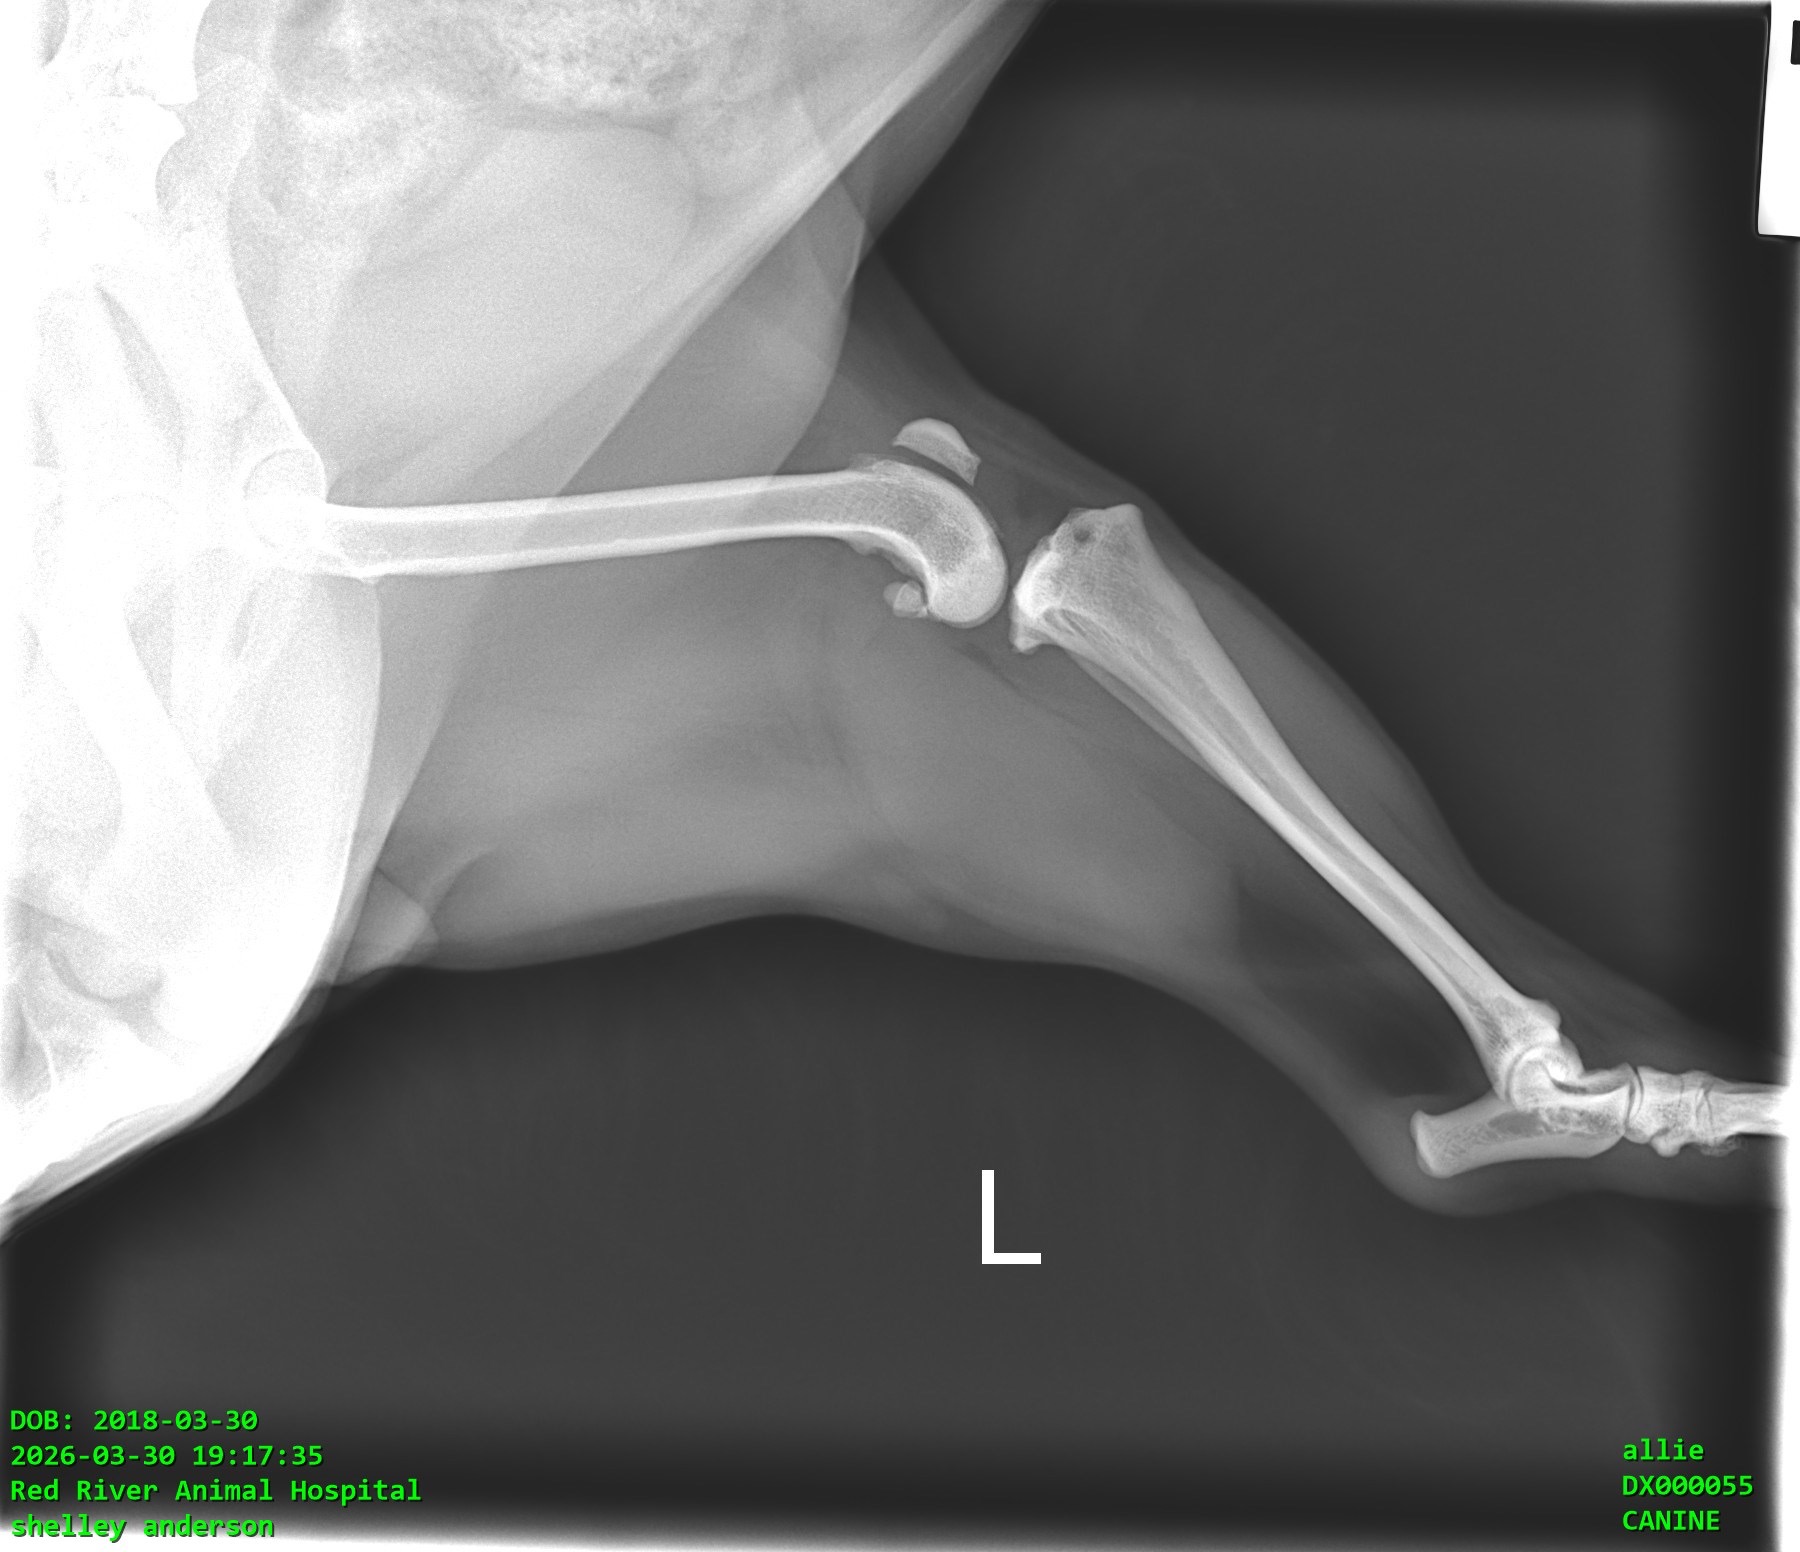

Allie is our 8-year-old Morkie, and she means absolutely everything to us, and especially to my mom. Allie is her whole world and goes everywhere with her. Recently, Allie was suddenly unable to put weight on her back leg. After taking her to the vet, we were told she has a torn ligament in her knee (CCL), which is very painful and requires surgery to properly fix.

Right now, she’s on pain medication and resting, but without surgery, there’s a risk of ongoing pain and long-term damage. We want to give her the best chance at a happy, comfortable life.

We were quoted between $5,000 and $5,500 for the surgery. If we don’t reach the full goal, the money will still go toward Allie’s care, like her medications, follow-up vet visits, rehabilitation, and possibly a more affordable surgical option or partial payment toward surgery. Nothing will go to waste, it will all be used for her treatment.